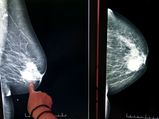

மார்பகங்களில் இப்படி திசுக்கள் இருந்தால் புற்றுநோய் வருமாம்... உடனே செக் பண்ணி பாருங்க...

மார்பக புற்று நோய்ப் பற்றி நீங்கள் தெரிந்து கொள்ள வேண்டிய விஷயங்கள்!!